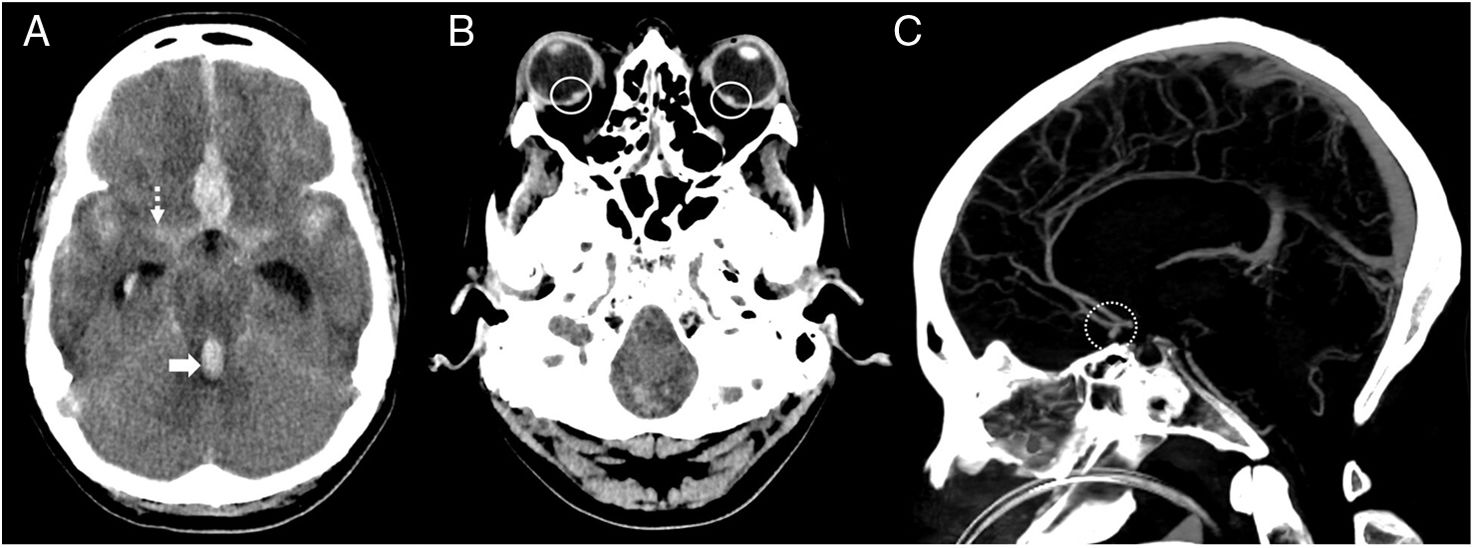

Spontaneous subarachnoid haemorrhage (SAH) is a neurological emergency that predominantly affects young adults, with a high mortality rate and severe neurological sequelae in survivors. Its most characteristic clinical manifestation is a sudden thunderclap headache, often described as the worst headache of one's life, and frequently accompanied by altered levels of consciousness and neck stiffness. Non-contrast cranial computed tomography (NCCT) is the initial diagnostic tool of choice due to its high sensitivity. Recognising the distribution patterns of haemorrhage on NCCT helps guide the aetiological diagnosis and assess the presence of complications such as hydrocephalus, intraventricular haemorrhage or cerebral oedema. This article offers a practical and detailed imaging-based guide for radiologists in the hyperacute phase of spontaneous SAH, distinguishing between aneurysmal, perimesencephalic and cortical patterns, and discusses their clinical, diagnostic and therapeutic implications.